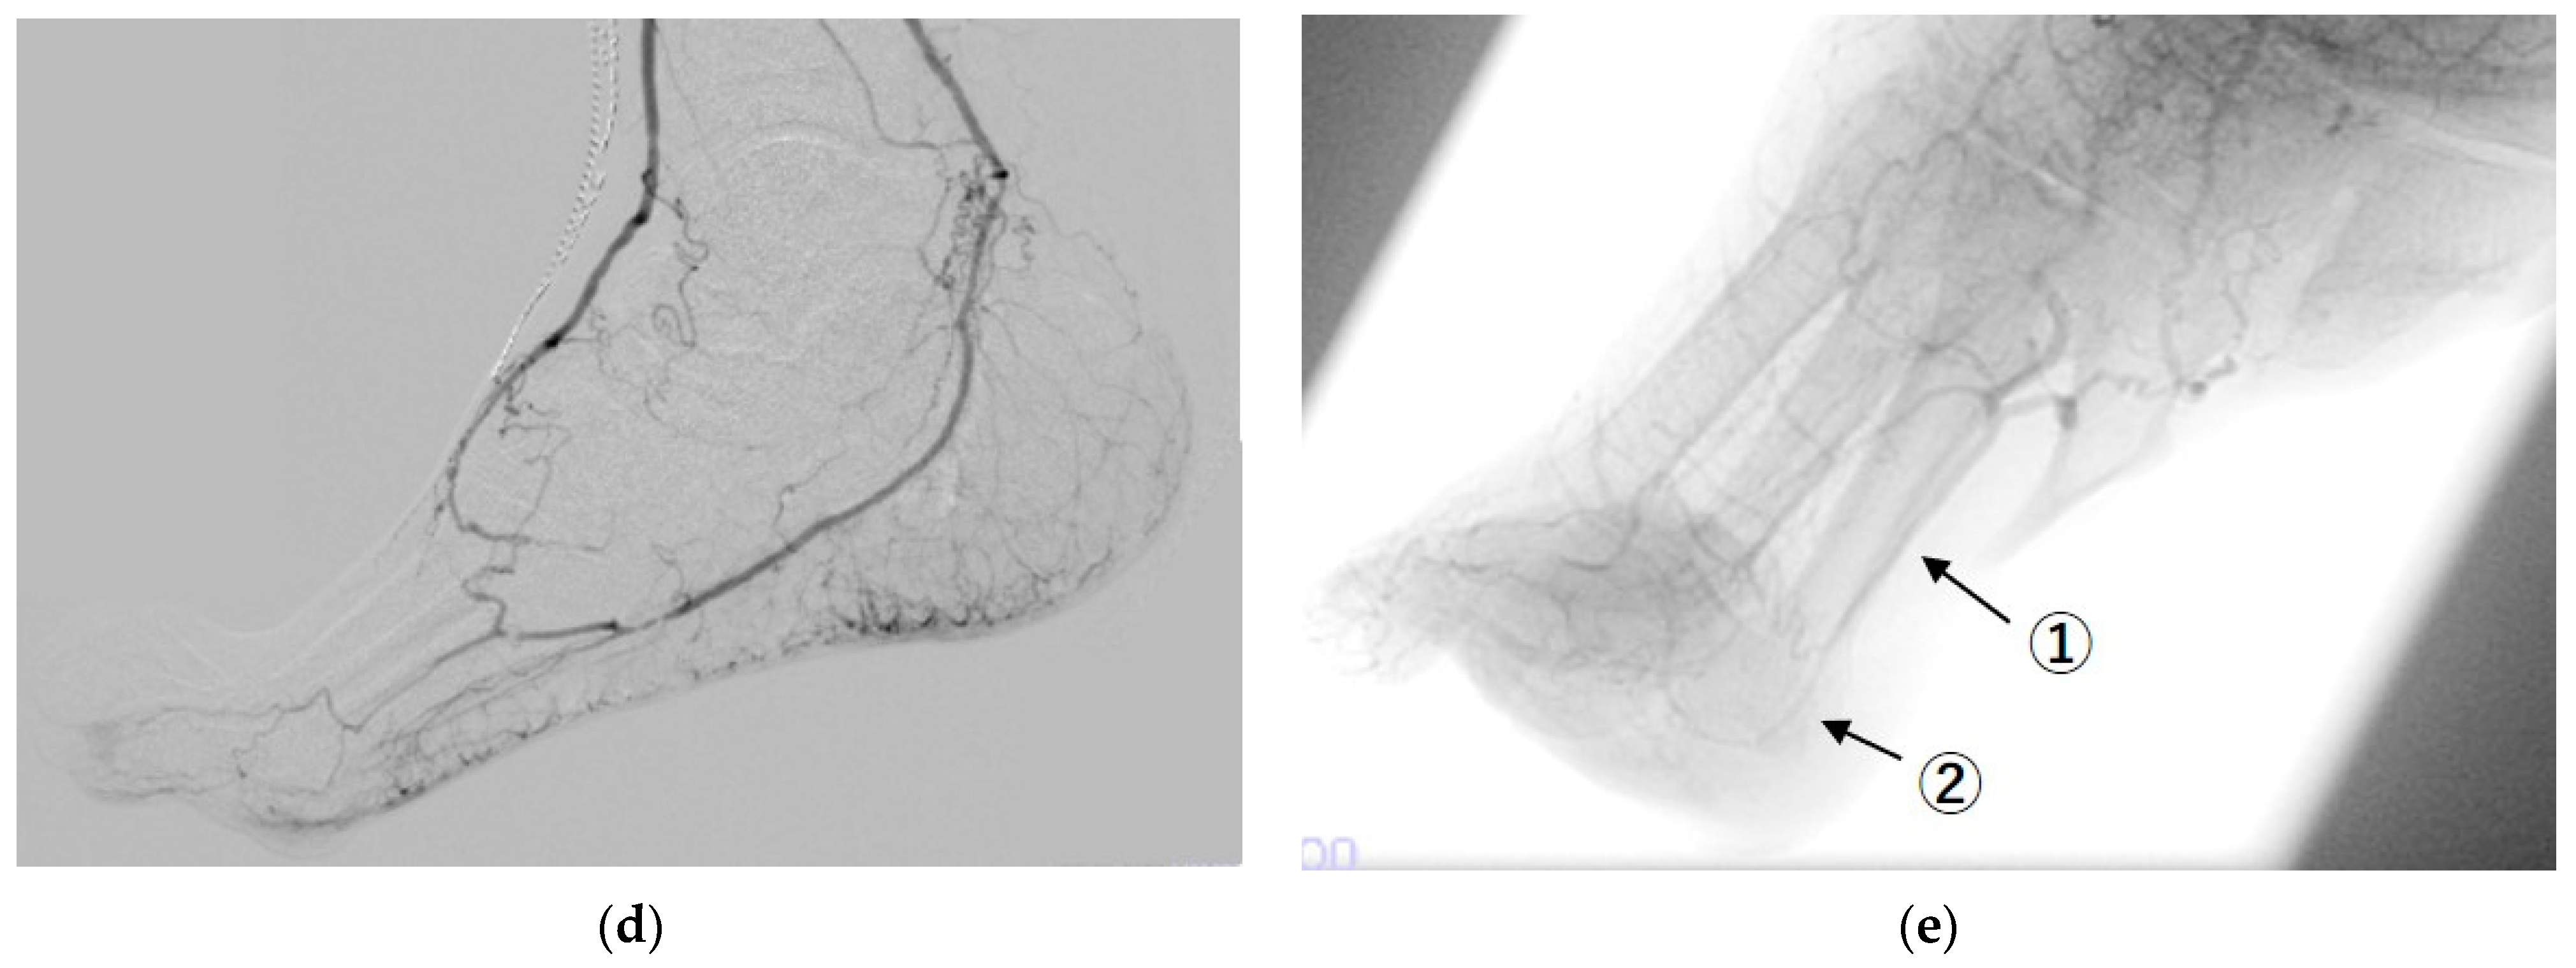

2.3. Revascularization